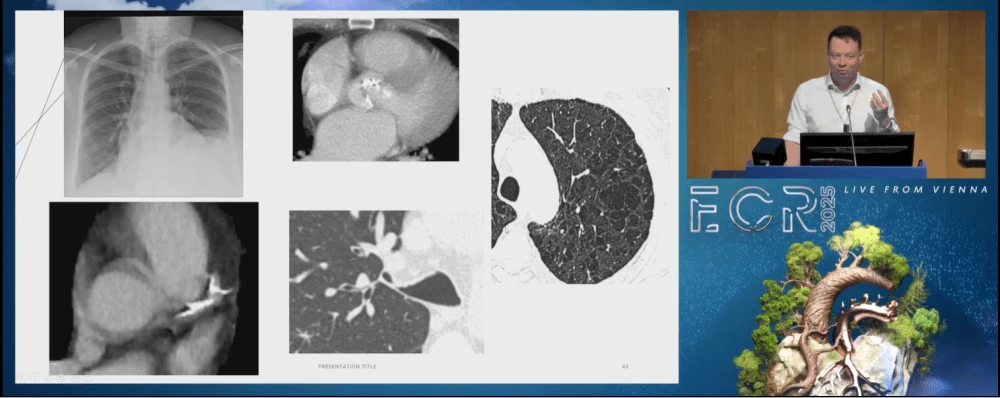

At the European Congress of Radiology (ECR), Joe Barnett, a radiologist from St Albans, UK, presented a session focused on improving chest CT reports. He highlighted the critical role of communication in radiology, drawing from his experience managing a radiology department. He noted that a significant portion of complaints in radiology stems from unclear communication. Additionally, his work with Heart Lung Health, the UK's largest lung cancer screening provider, has involved developing structured template reports to enhance the efficiency and safety of radiologists.

The solution, according to Barnett, is structured template reporting. He explained that a template report follows a standardised format, ensuring uniformity in structure and terminology. This approach not only makes reports clearer but also reduces variability, ensuring that essential findings and recommendations are always included. “A template report is uniform. It never varies. It’s got a consistent, uniform structure and a standardised lexicon,” he said. For example, in lung cancer screening, a template ensures that every report includes whether certain findings are present or absent, eliminating ambiguity.